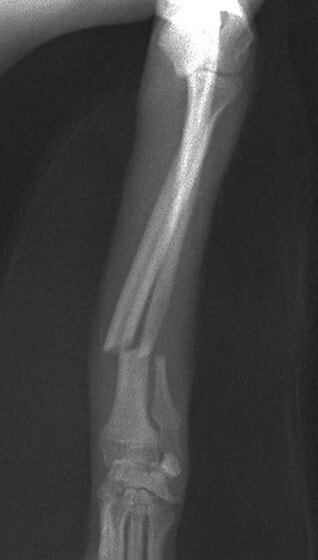

症例3:キルシュナーワイヤーのピンニングによる整復

ペルシャ猫 11ヶ月齢 雄

他院にて左大腿骨遠位の成長板骨折(salter-harrisⅠ型)が認められており、治療相談を目的として来院。当院にて、キルシュナーワイヤーを用いたピンニングにより骨折部位の整復を行いました。術後の経過は良好で、現在も経過観察中です。

術前レントゲン

術後レントゲン